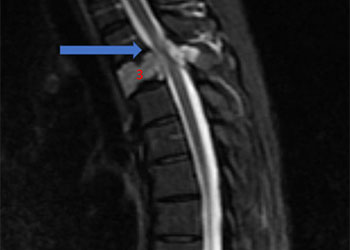

Spine:

Thoracic Spinal Cord Tumor Case Presentation

Author: Xavier P. J. Gaudin D.O., F.A.C.O.S., Read More!